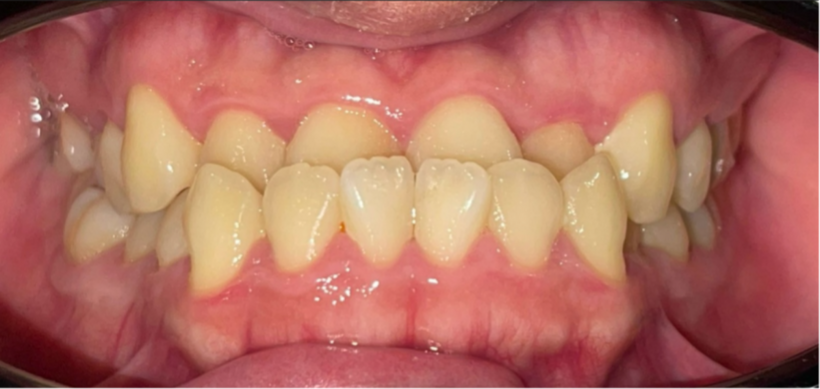

Trước khi tiến hành niềng răng, Nhật Hào gặp phải tình trạng răng chen chúc nghiêm trọng ở cả hai hàm kèm khớp cắn ngược hạng 3 (móm). Hàm dưới của Hào đưa ra quá nhiều khiến khuôn mặt lệch, việc ăn nhai rất khó khăn. Mỗi khi nhai đồ cứng, Hào thường cảm thấy rất đau vùng thái dương. Điều đáng sợ hơn là nhữncơn đau đầu âm ỉ kéo dài

Khi đi khám răng, bác sĩ mới xác định Hào bị rối loạn khớp thái dương hàm do sai khớp cắn nặng và đây cũng là nguyên nhân khiến cho cậu bị đau đầu thời gian dài. Nhật Hào đã quyết định niềng răng. Gần một năm chỉnh nha, hàm răng của Hào đã được đưa về đúng vị trí. Từ khuôn mặt bị móm và lệch, nay đường nét đã hài hòa, nụ cười tự nhiên và rạng rỡ hơn. Điều quan trọng nhất là Hào đã cải thiện đáng kể triệu chứng đau đầu.